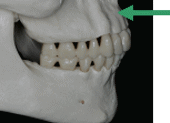

1.下顎歯列弓の前方限界

![]() |

下顎前歯の根尖の位置 |